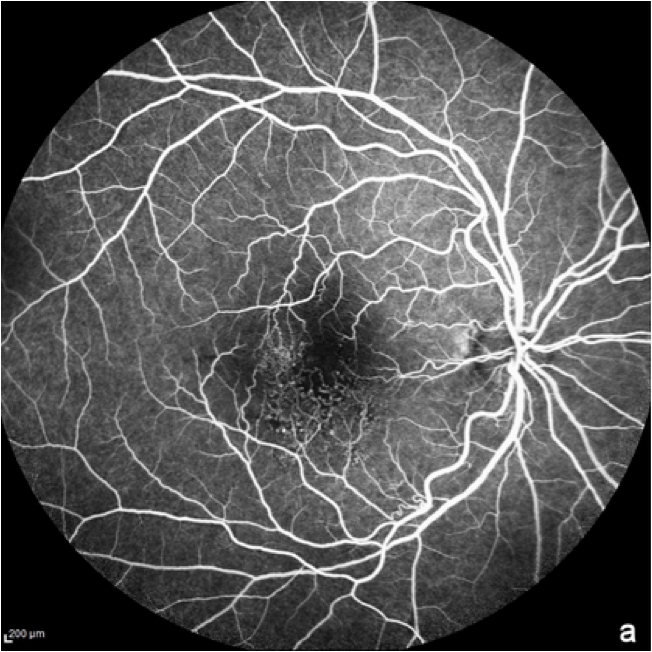

Angiografía de fondo de ojo con fluoresceína (AGF)

En la angiografía con fluoresceína, se inyecta por vía intravenosa un colorante fluorescente para obtener imágenes de los vasos sanguíneos de la retina.11 La AGF se utiliza normalmente para excluir el diagnóstico de DMAE húmeda. También puede utilizarse en la DMAE seca o en la atrofia geográfica, ya que las regiones atróficas presentan una mayor fluorescencia debido a la muerte del epitelio pigmentario de la retina (EPR).8

Las imágenes de AGF muestran detalles de la vasculatura de la retina, así como la eliminación del colorante en las partes normales de la retina y la continuidad de la fluorescencia en las zonas con anomalías de la retina.12